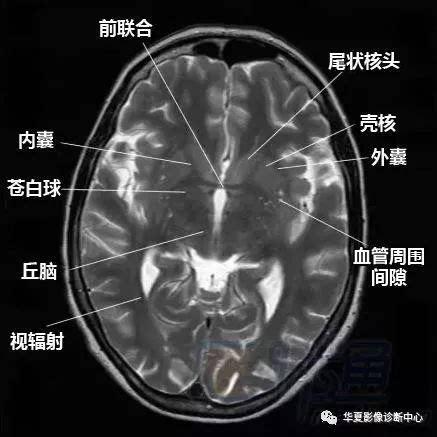

脑部断层 内囊 willis环 前联合 垂体 海马:清晰解剖图谱